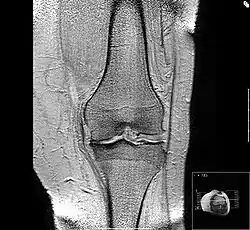

-

MRI of osteoarthritis in the knee, with characteristic narrowing of the joint space